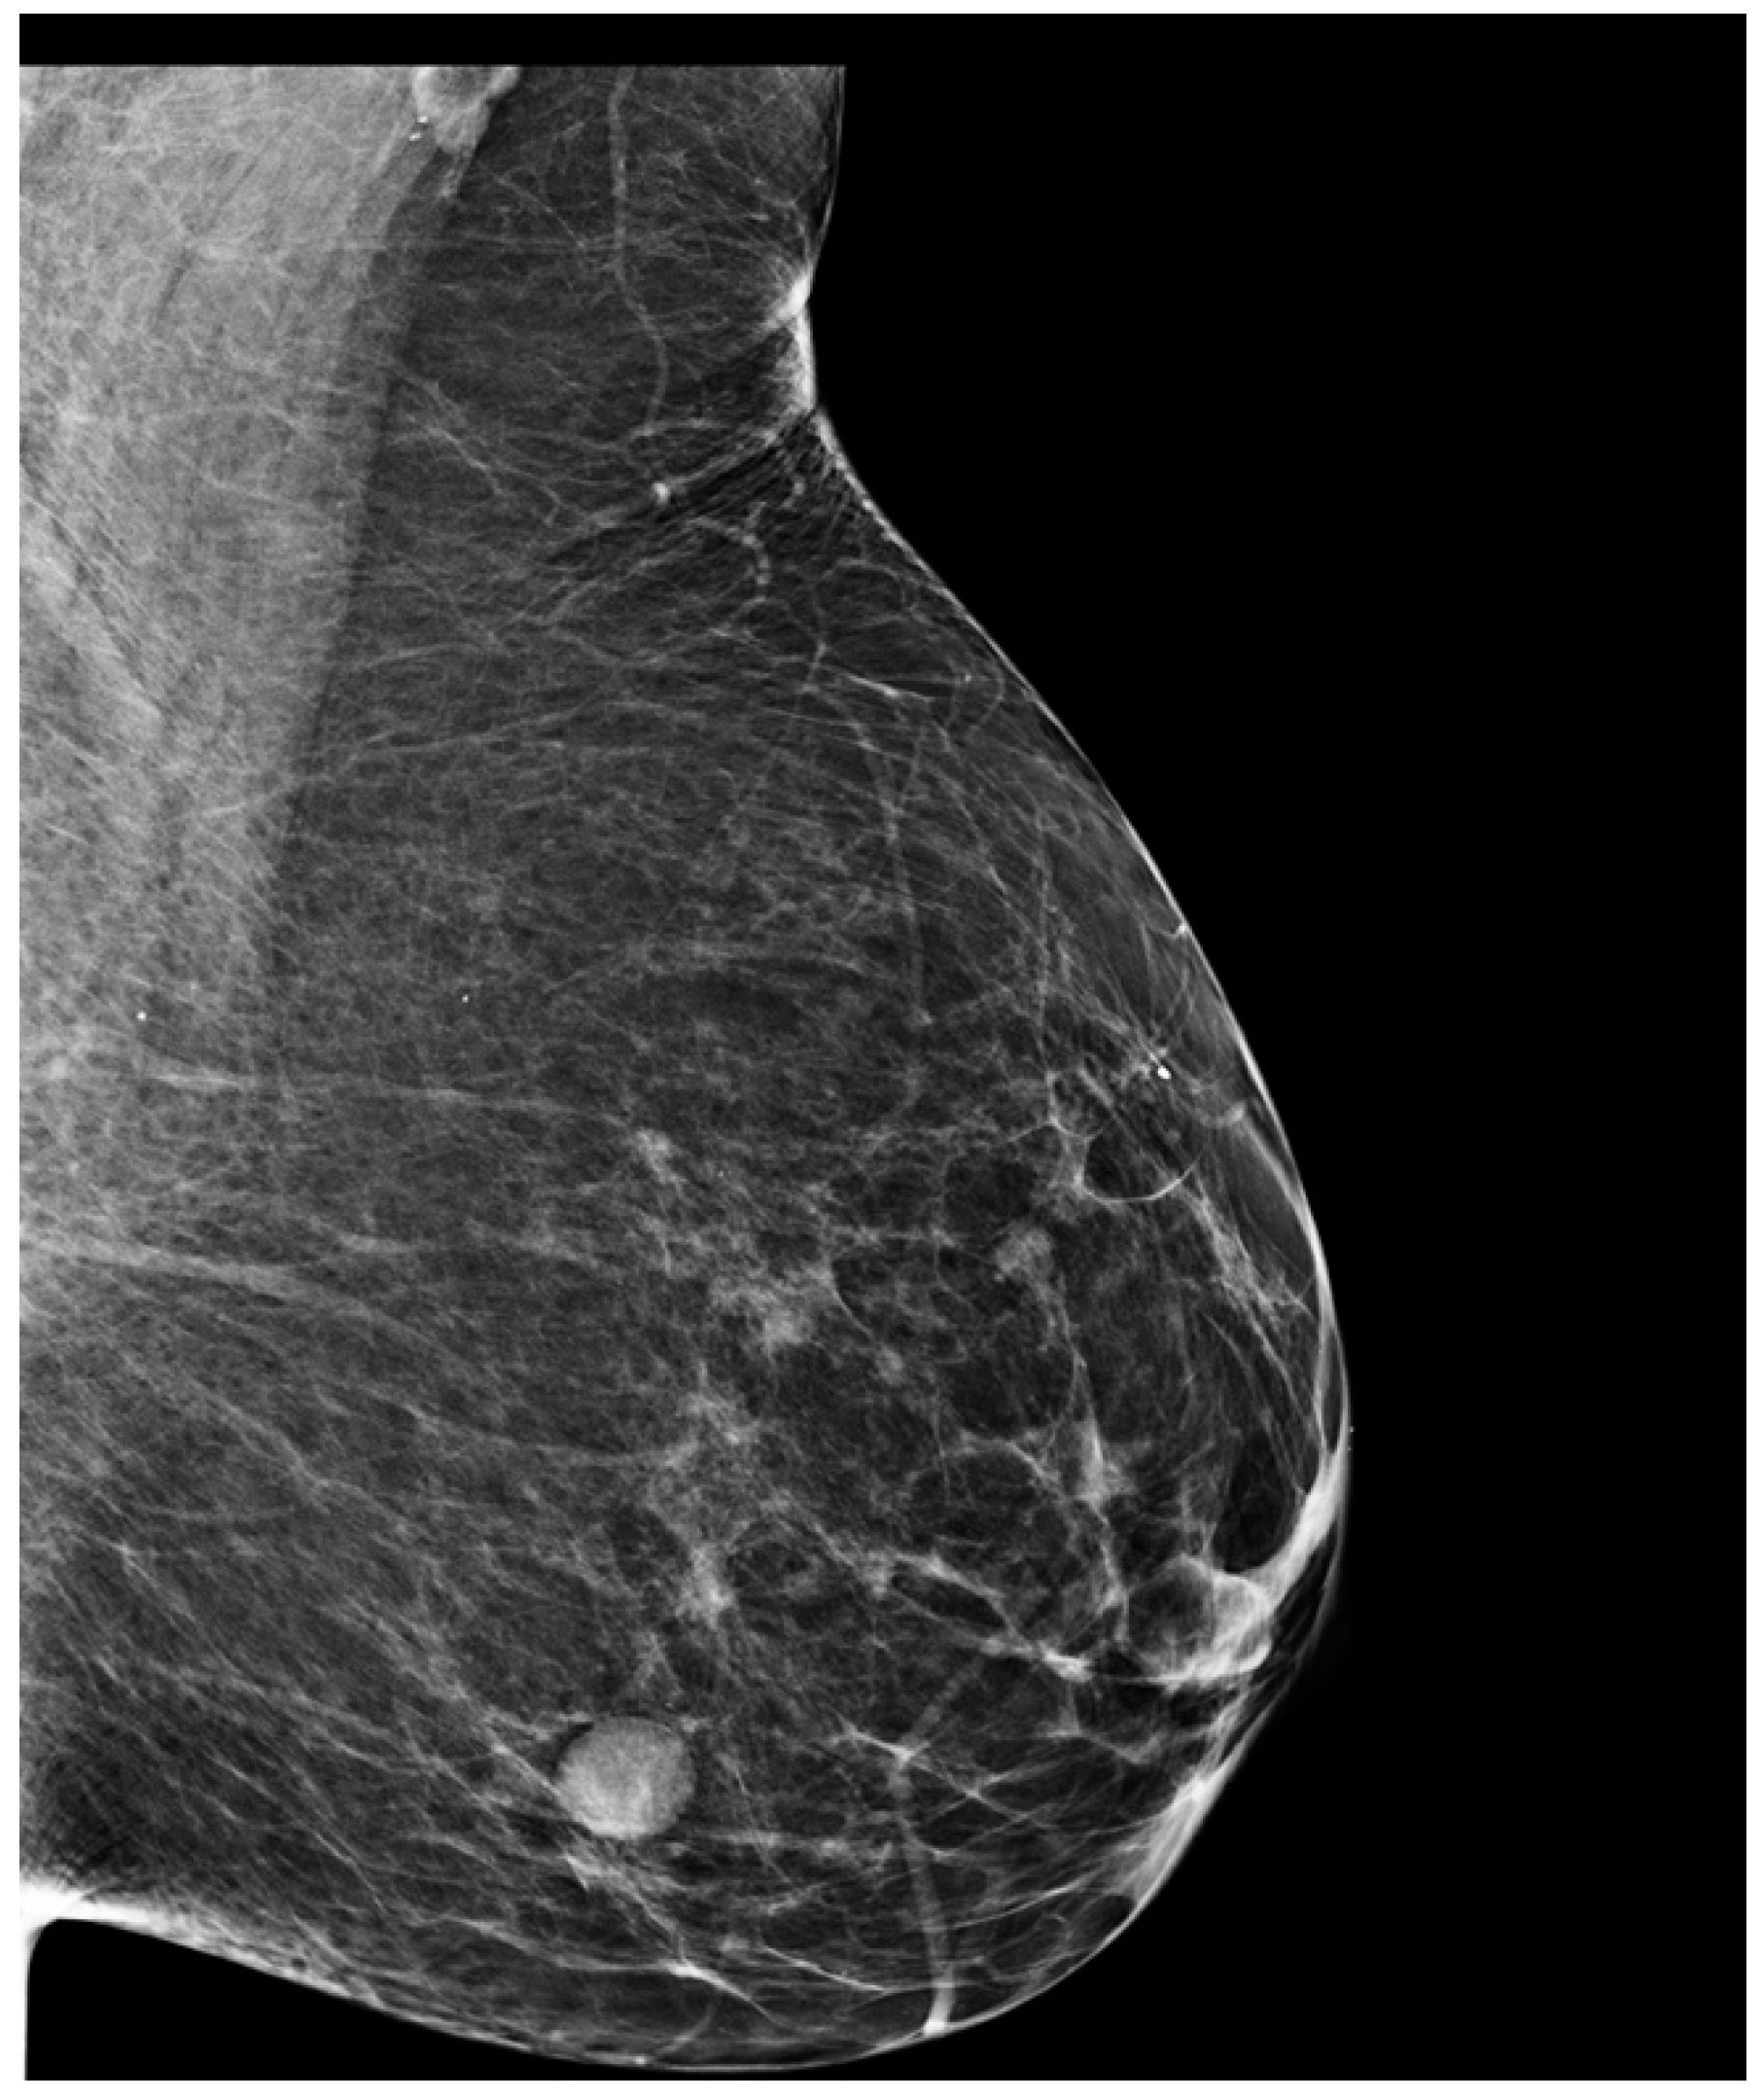

3. Case Presentation